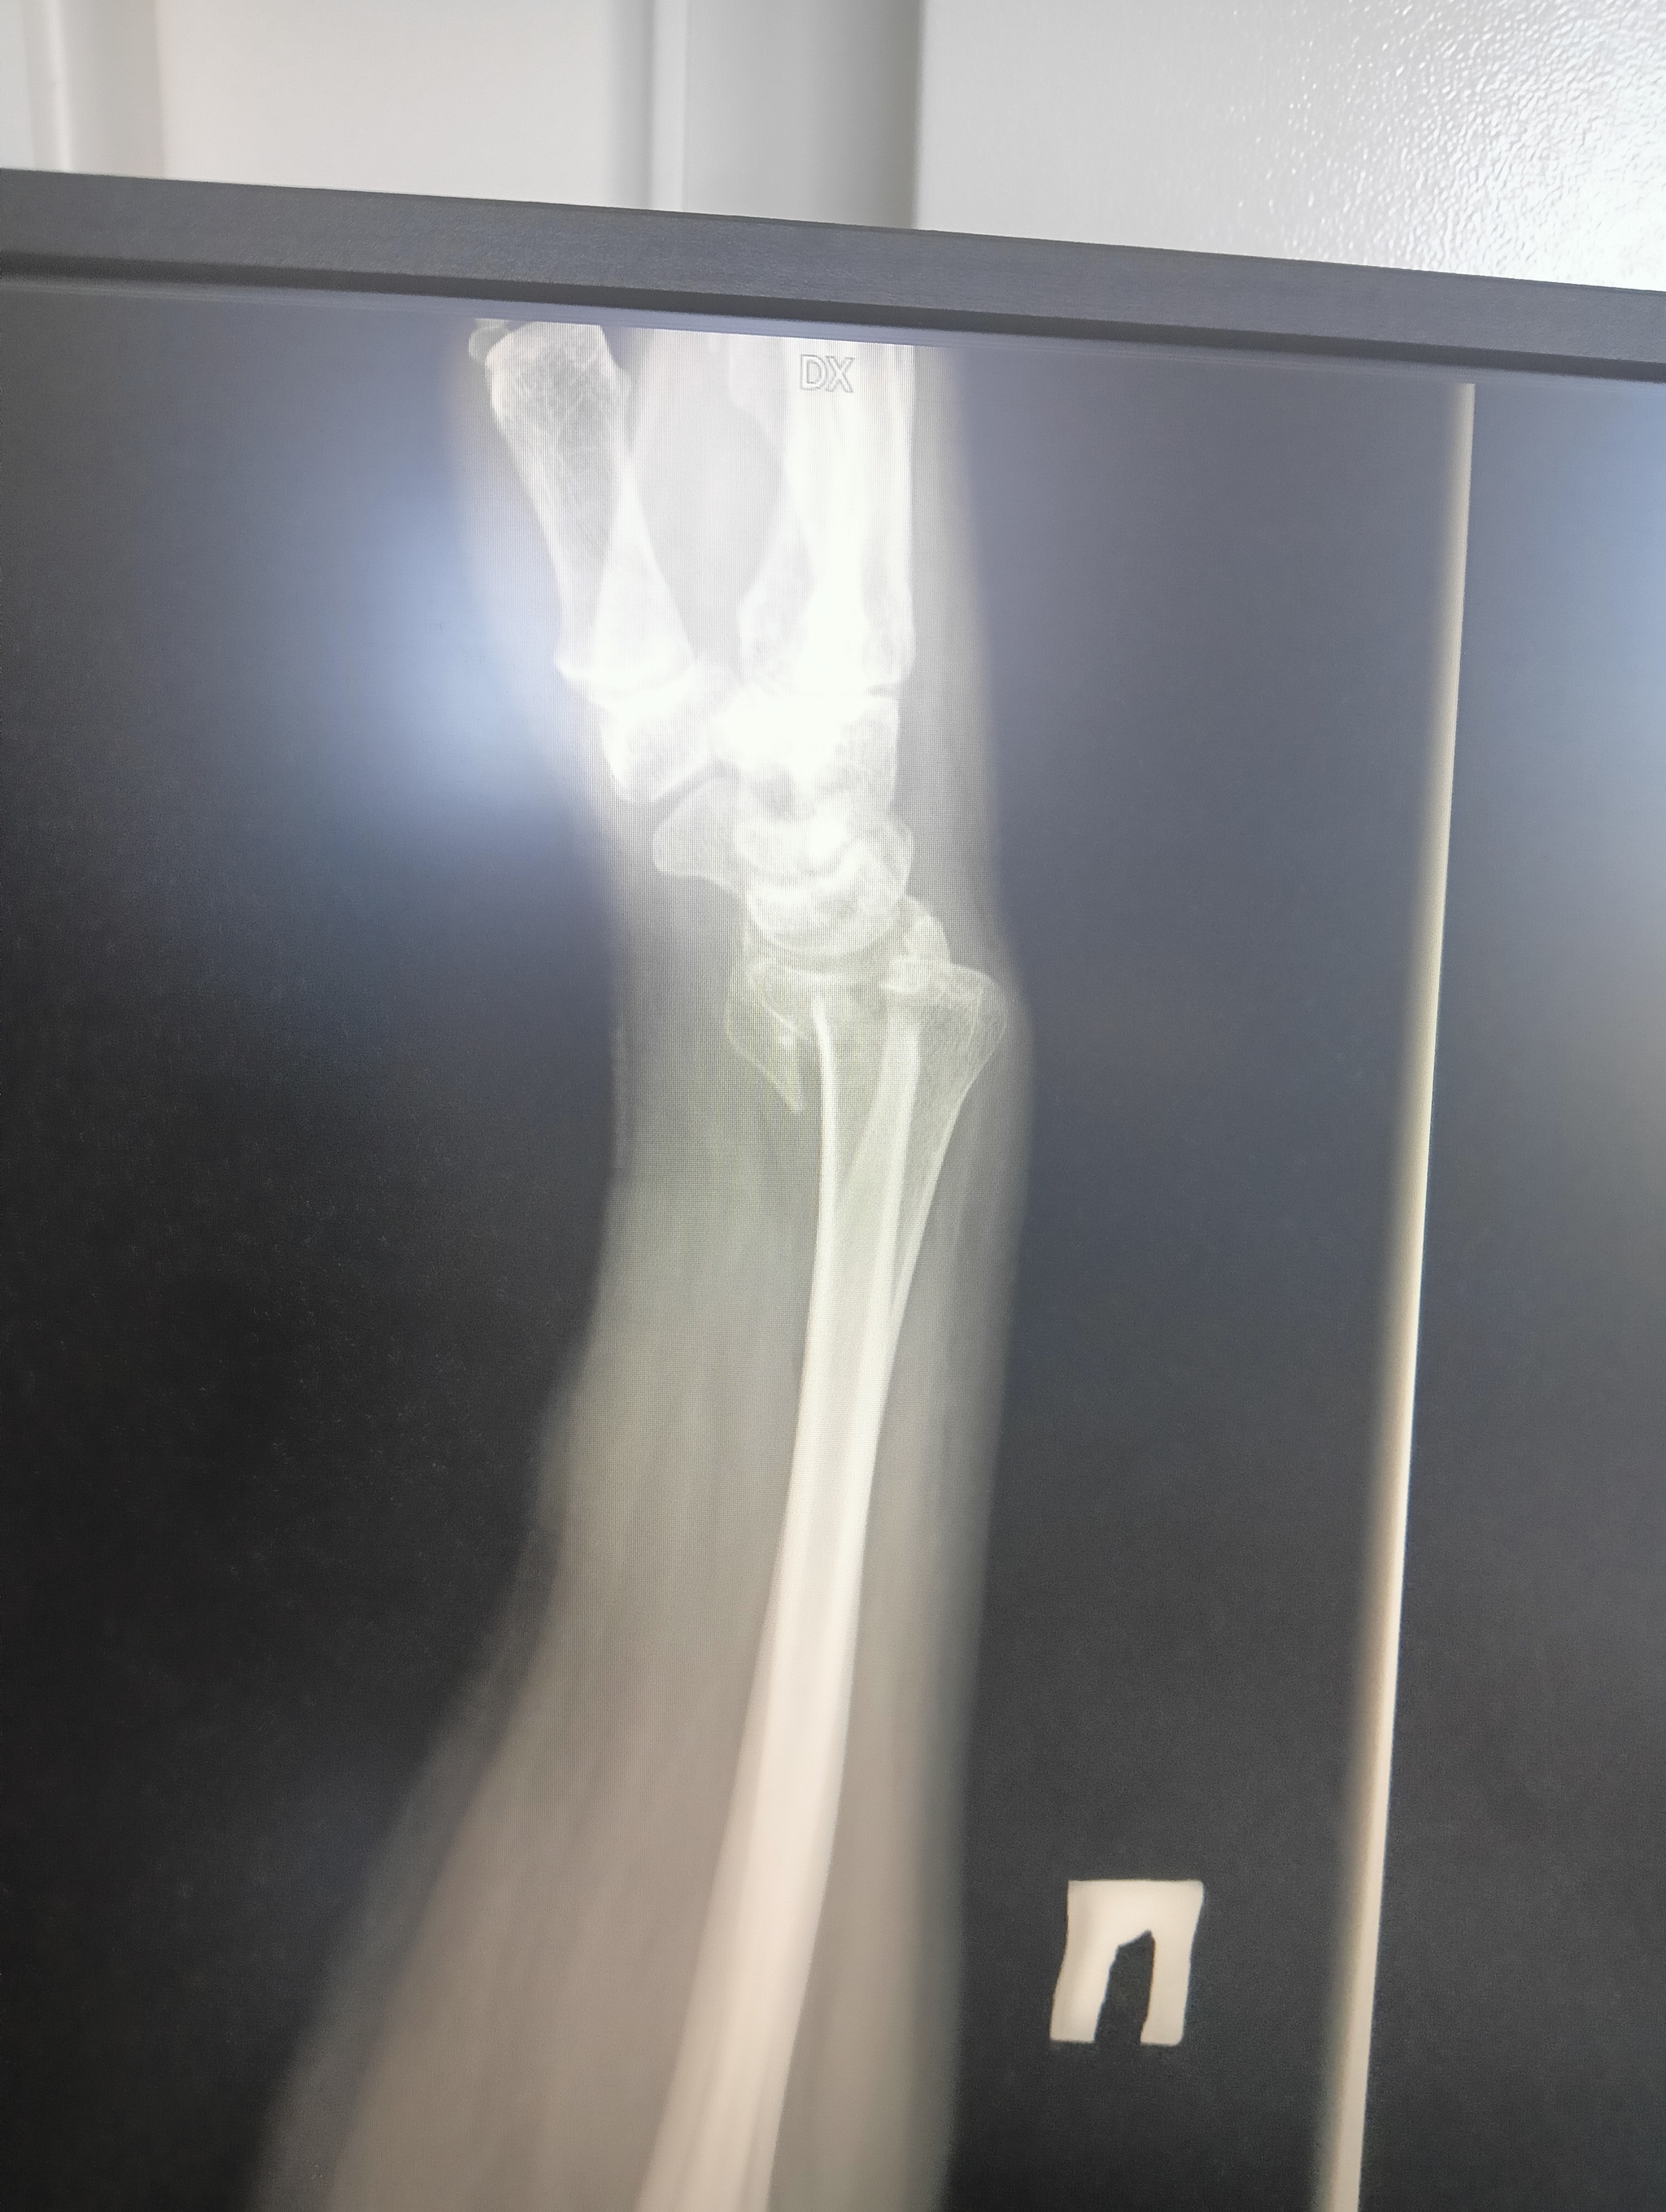

22 июля я неудачно упала и получила оскольчатый перелом дистального метафиза лучевой кости со смещением отломков более чем на 1/2 ширины диафиза. Открытый перелом шиловидного отростка локтевой кости. Была месяц в гипсе, но ничего не срослось. Диастаз костных отломков стал до 4 мм. Локтевая ушла в сторону на 5 мм. На 3 месяц после перелома мне сделали операцию, поставив титановую пластину. Сегодня сделала ренген и получила вот такой результат: Застарелый сомнительно консолидирующийся перелом дистального метафиза правой лучевой кости в условиях накостного МОС. Помимо отрыва шилообразного отростка локтевой кости, видно, имеется разрыв дистального радио-ульнарного сочленения.

Как я понимаю, Шиловидный отросток не прирос и стал болтаться, травмировав ткани внутри... Возможно, что это от реабилитации, я прохожу maps терапию для разработки руки, а может и просто, ведь рукой стараюсь пользоваться.

в ччетверг еду к хирургу, который меня оперировал. Но очень интересно мнение. Нужна ли тут операция и какая...

верхние ффото через 2 месяца после перелома, потом после операции и 2 нижние - сегодня